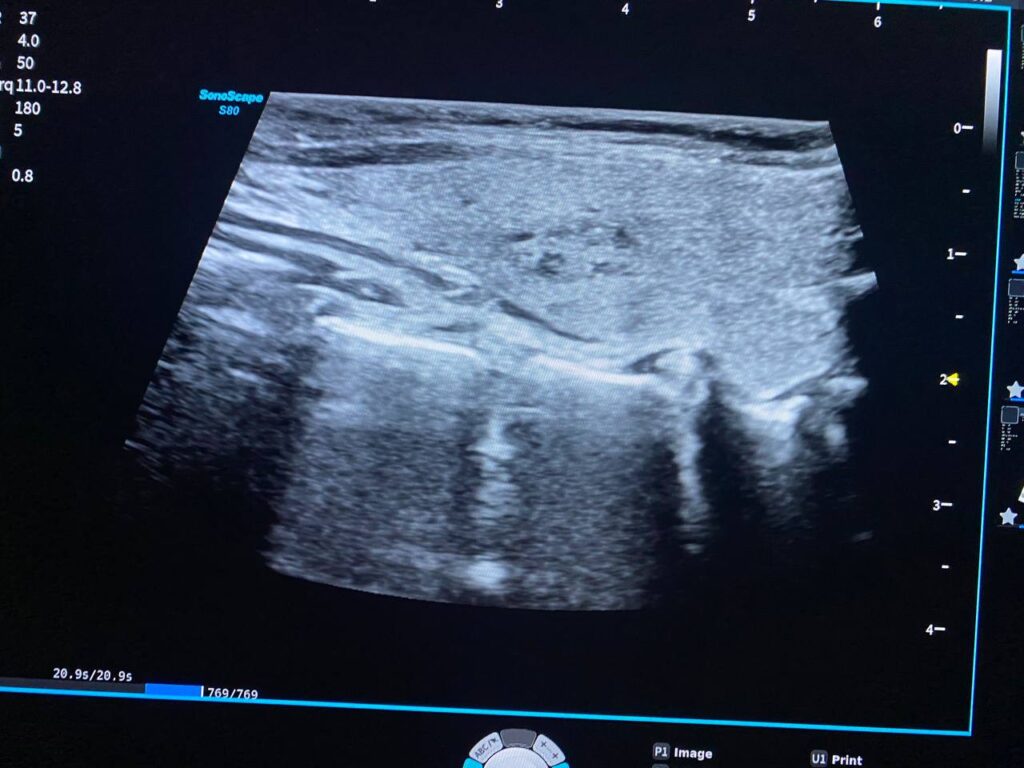

Right lobe size = 31x57x25mm, normal in texture, contain heterogenous circumscribed nodule 33x18mm, contain macrocalcification , mostly benign , TIRADS 3 , For short interval follow up